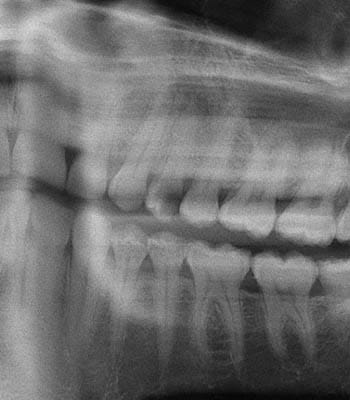

Dental implants are a titanium "root" which can be placed into the jawbone. Once integrated with your bone, the implant can be used to support a crown, a bridge, or secure a complete denture. Dental implants may be used to eliminate partial plates and dentures. The success rates for dental implants are extremely high which is due in part to the fact that root-form implants are made of a biocompatible material, titanium.

Below are a few examples of what DENTAL IMPLANTS can do for you and your smile!